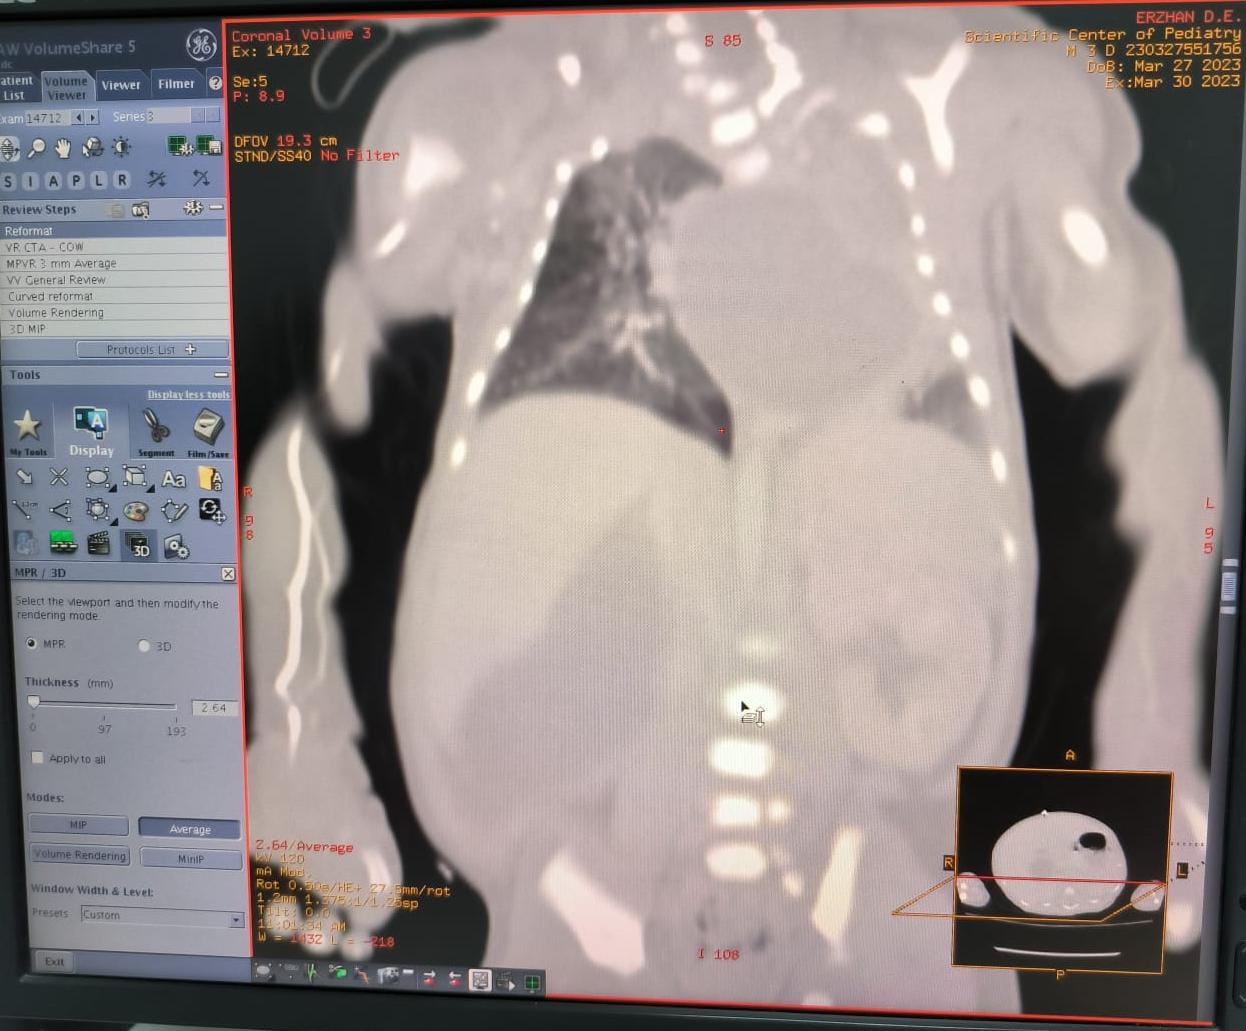

On the basis of computed tomography, a preliminary diagnosis was made: multiple doubling of the digestive system, thoracoabdominal form. Doubling of the esophagus, doubling of the intestines. Within five days, the condition was corrected. Surgical treatment was performed urgently, thoracotomy on the left, excision of the doubled part of the esophagus, laparotomy by excision of the duodenum duplication and resection of the tubularly doubled portion of the small intestine with anastomosis were performed at the same time.